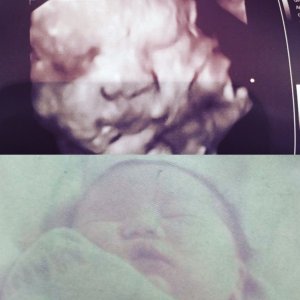

Just for fun, here’s the 4D image of Damy and my husband’s first picture as a newborn. They look so much alike!